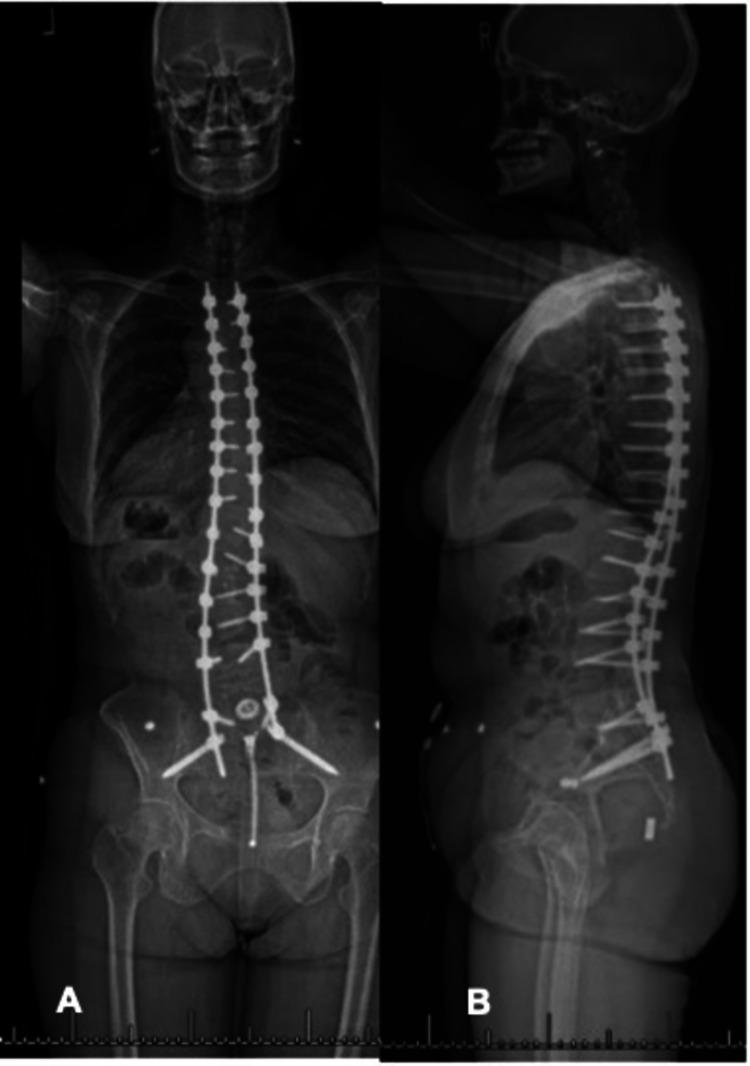

Limited unilateral instrumentation has been used in the past in the treatment of adolescent idiopathic scoliosis; however, to our knowledge, there are no reported cases with ultra-long follow up regarding this. Our objective is to report on the 43-year follow-up of limited Harrington rod instrumentation for the treatment of a double major adolescent idiopathic scoliosis curve. We describe the patient's initial presentation, including history, physical exam, radiographic findings and clinical decision-making. Initial coronal cobb angle measurements before surgery were: 14° T1-T5, 42° T5-T12, 44° T12-L4. At 43 years of follow up, there was progression (14°>24°, 42°>70°, 44°>50°) of the patient's double major scoliosis curve despite unilateral, limited Harrington rod instrumentation from L4-S1. The patient was treated with a T3-pelvis instrumentation and fusion and posterior column osteotomies. To our knowledge, this is the longest follow-up and subsequent revision of a patient undergoing limited, unilateral Harrington rod instrumented fusion for the treatment of a double major adolescent idiopathic scoliosis curve.

过去曾采用有限的单侧器械治疗青少年特发性脊柱侧凸;然而,据我们所知,尚无关于此治疗方法的超长随访报告病例。我们的目的是报告对一名双主弯青少年特发性脊柱侧凸患者采用有限的哈灵顿棒器械治疗后的43年随访情况。我们描述了患者的初始表现,包括病史、体格检查、影像学检查结果及临床决策。手术前初始冠状面 Cobb 角测量值为:T1 - T5 为14°,T5 - T12 为42°,T12 - L4 为44°。在43年的随访中,尽管对该患者从L4 - S1进行了单侧有限的哈灵顿棒器械治疗,但双主弯脊柱侧凸仍有进展(14°>24°,42°>70°,44°>50°)。该患者接受了T3 - 骨盆器械固定融合及后路截骨术。据我们所知,这是对一名接受有限单侧哈灵顿棒器械固定融合治疗双主弯青少年特发性脊柱侧凸患者的最长随访及后续翻修情况。